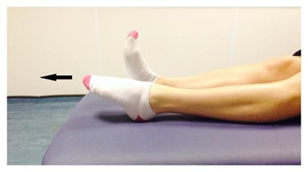

- Point your foot up and down. Repeat this 10 times.